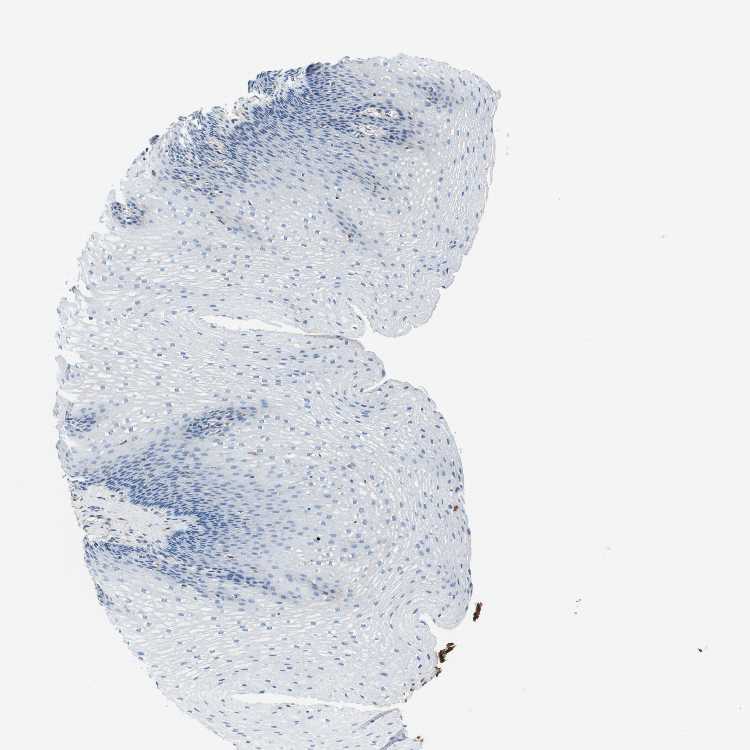

ESOPHAGUS - Antibody stainingi

Antibody staining in the annotated cell types in the current human tissue is reported as not detected, low, medium, or high, based on conventional immunohistochemistry profiling in selected tissues. This score is based on the combination of the staining intensity and fraction of stained cells.

Each image is clickable and will lead to virtual microscopy that enables deeper exploration of all samples and also displays staining intensity scores, fraction scores and subcellular localization as well as patient and tissue information for each sample.

Antibody CAB012703

Squamous epithelial cells Not detected

Male, age 38

Esophagus sample 131

nTPM: 0

overview

Male, age 76

Esophagus sample 132

nTPM: 1.5